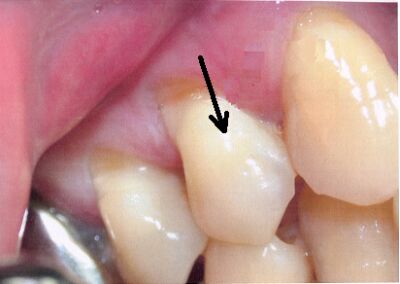

43.有關下圖上顎恆犬齒的敘述,下列何者正確? (A)正確診斷為上顎恆犬齒轉位(transposition) (B)此時拔除右上乳犬齒,有助於改變恆犬齒的萌發方向 (C)此時拔除恆犬齒為最適合的選擇 (D)錐狀束電腦斷層(CBCT)可以輔助診斷及決定治療方式